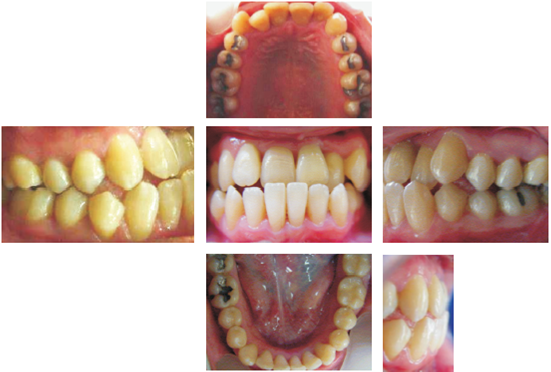

De igual forma se sometió a cirugías periodontales de los 4 sextantes y estuvo bajo tratamiento de control de placa y bolsas por 3 años. El análisis facial indica una retrusión maxilar, líneas medias desviadas en ambas arcadas y perfil Clase III por hipoplasia maxilar corroborada por la depresión malar bilateral; el ángulo nasolabial cerrado que compromete la estética del perfil y la línea de sonrisa negativa no permite que se observe más del 25% de los dientes superiores y la sobreerupción de los incisivos inferiores que producen una exposición de 3 mm (Figura 1).

Dentro de su lista de problemas dentales se encontraba la línea media dental desviada en ambas arcadas, retroinclinación de dientes superiores y proinclinación de dientes inferiores aunado al apiñamiento (Figura 2).

Figura 2 Se observa clase III molar izquierda y derecha, clase II canina derecha, clase III canina izquierda, mordida cruzada anterior, línea media desviada dental y mandibular, apiñamiento bimaxilar, retroinclinación de superiores y proinclinación de inferiores.

Bolsas periodontales sin sangrado de 4 a 6 mm en el segmento anterior superior e inferior con pérdida de cresta ósea (Cuadro I y figura 3).